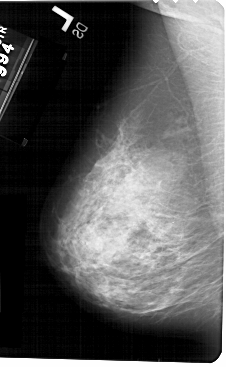

A_1511_1.LEFT_MLO

LEFT_MLO LINES 5491 PIXELS_PER_LINE 3376 BITS_PER_PIXEL 12 RESOLUTION 43.5 NON_OVERLAY